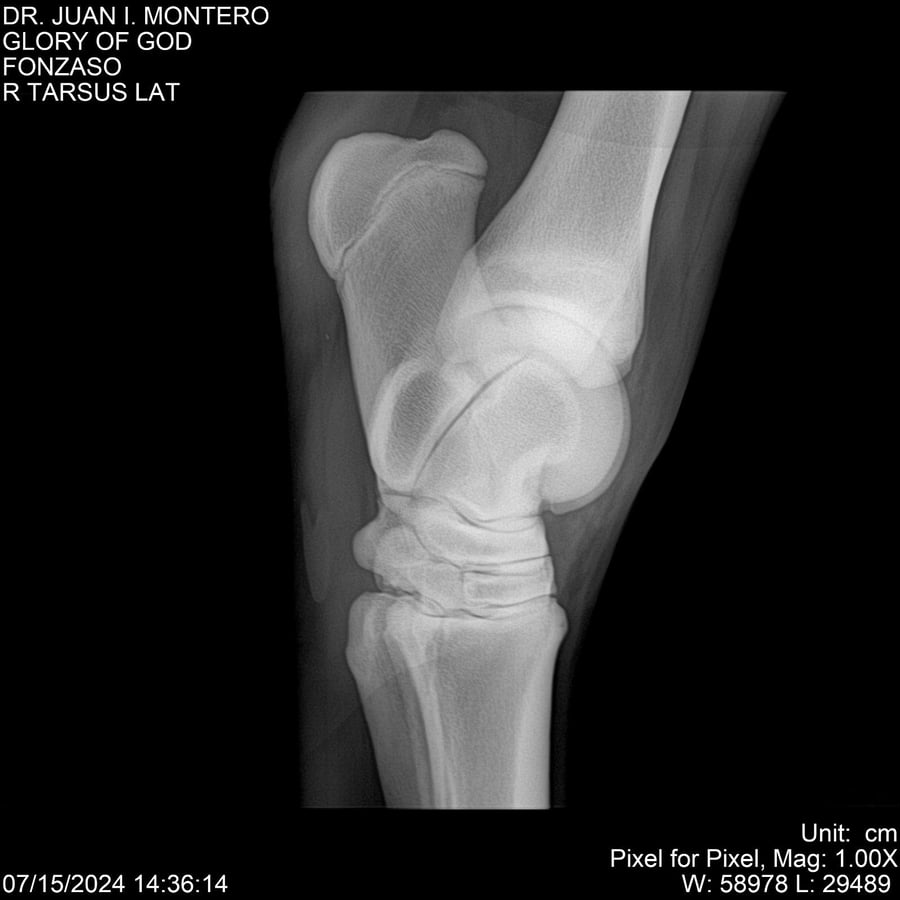

LOTE 10, GLORY OF GOD 🔥 🔥 🔥 Lote Anterior Volver al remate Lote Siguiente Ficha Contacto Montevideo - Ficha del Lote Identificador: #281389 Categoría: Yeguarizos Montevideo - 115 Visualizaciones ClicData Contacto Empresa: Abelenda N. R., Walter Hugo Nombre*: Teléfono* : E-mail* : Mensaje Enviar Registrese gratis Este contenido Exclusivo está disponible sólo para usuarios registrados Ingresar